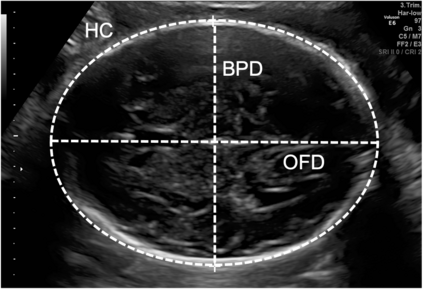

Deep-learning (DL) algorithms are becoming the standard for processing ultrasound (US) fetal images. Despite a large number of survey papers already present in this field, most of them are focusing on a broader area of medical-image analysis or not covering all fetal US DL applications. This paper surveys the most recent work in the field, with a total of 145 research papers published after 2017. Each paper is analyzed and commented on from both the methodology and application perspective. We categorized the papers in (i) fetal standard-plane detection, (ii) anatomical-structure analysis, and (iii) biometry parameter estimation. For each category, main limitations and open issues are presented. Summary tables are included to facilitate the comparison among the different approaches. Publicly-available datasets and performance metrics commonly used to assess algorithm performance are summarized, too. This paper ends with a critical summary of the current state of the art on DL algorithms for fetal US image analysis and a discussion on current challenges that have to be tackled by researchers working in the field to translate the research methodology into the actual clinical practice.